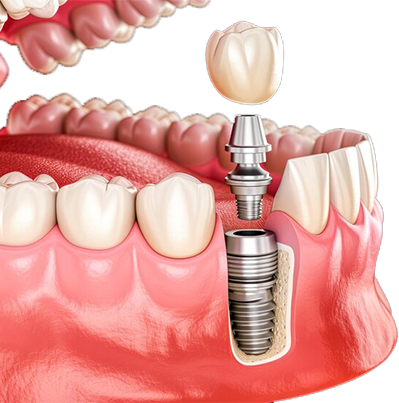

Dental Implants

Permanent tooth replacement solutions that restore natural function, strength, and appearance while improving confidence and long-term oral health.